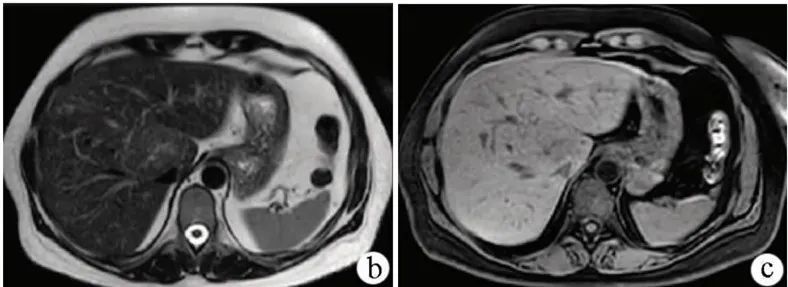

诊断:FNH的诊断主要依靠影像学和分子病理学检查。常用的检查方法有超声、CT、MRI和血管造影等。联合应用可提高其确诊率。

图4 免疫组化

图5 MRI图像

图6 造影剂增强图像